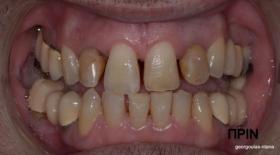

ΠΡΟΣΘΕΤΙΚΗ ΑΠΟΚΑΤΑΣΤΑΣΗ ΣΤΗΝ ΑΝΩ Κ ΚΑΤΩ ΓΝΑΘΟ ΚΑΙ ΤΟΠΟΘΕΤΗΣΗ ΕΜΦΥΤΕΥΜΑΤΩΝ ΜΕ ΚΛΕΙΣΤΗ ΑΝΥΨΩΣΗ ΙΓΜΟΡΕΙΟΥ

Ο ασθενής  προσήλθε στο ιατρείο μας θέλοντας να βελτιώσει την εμφάνιση των πρόσθιων δοντιών του και να αποκαταστήσει την υγεία κ την λειτουργία όλου του στόματος. Πραγματοποιήθηκε περιοδοντική θεραπεία κ ενδοδοντικές θεραπείες (απονευρώσεις) όπου κρίθηκε απαραίτητο και στη συνέχεια τοποθετήθηκαν 3 εμφυτεύματα, 2 δεξιά στις θέσεις του πρώτου κ δεύτερου γομφίου κ 1 αριστερά στη θέση του πρώτου προγομφίου. Κατά την  τοποθέτηση των 2 εμφυτευμάτων της δεξιάς πλευράς, πραγματοποιήθηκε κλειστή ανύψωση ιγμορείου με το σύστημα Piezotome-Intralift , τεχνική που εξασφαλίζει τη μικρότερη δυνατή επέμβαση κ τη μικρότερη μετεγχειρητική ταλαιπωρία (minimally invasive), καθώς κ αυξητικους παράγοντες PRF. Σε όλη τη διάρκεια της θεραπείας  ο ασθενής ήταν καλυμμένος τόσο αισθητικά όσο και λειτουργικά με προσωρινές μεταβατικές αποκαταστάσεις. 4 μήνες μετά την  τοποθέτηση των εμφυτευμάτων κ την οστεοενσωμάτωσή τους, ακολούθησε η τοποθέτηση των μόνιμων αποκαταστάσεων.